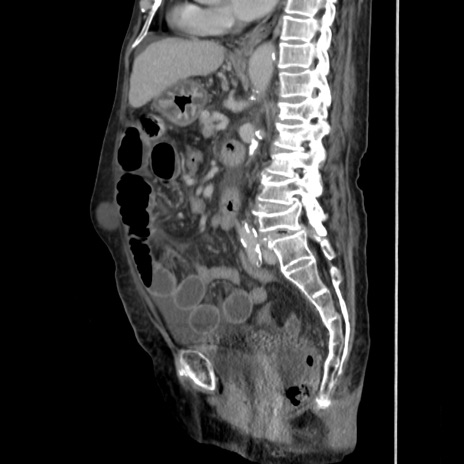

症例31(矢状断像)

【症例】80歳代 女性

【主訴】腹部膨満感

【現病歴】他院にて肝硬変にてフォロー中。1週間前から便秘、腹部膨満感、臍部腫瘤あり受診となる。

【既往歴】肝硬変

【身体所見】腹部膨隆あり、皮膚変化なし、疼痛なし。

【データ】WBC 4600、CRP 0.25